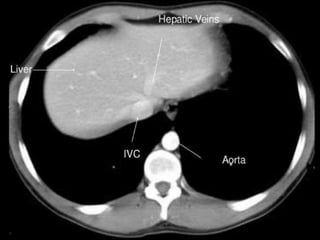

CT cross sectional anatomy.

CT – computedtomography. •Cross-sectional modality with capabilities for multiplanar reconstruction and dynamic imaging to assess vascularity •Tube rotates around the body and a circle of stationary detectors detects the penetrating x-rays forming an image.